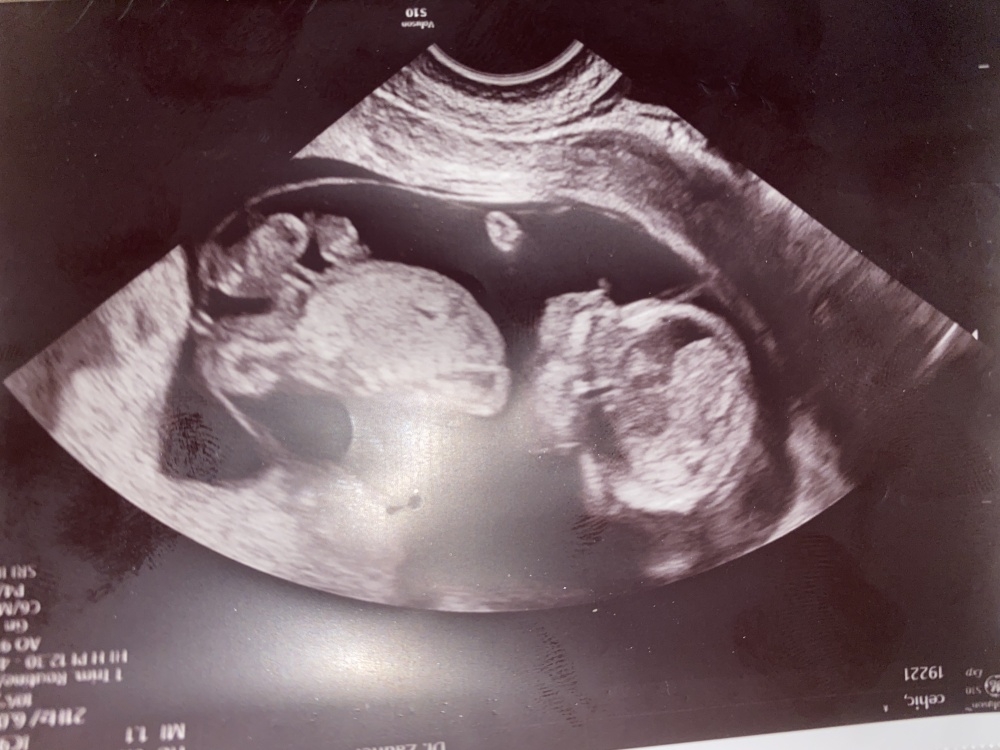

Bin mit meinem 2. Baby in der 18 Ssw, habe in der 12. Woche Tendenz Junge und in der 17. Woche Tendenz Mädchen bekommen 🙈 was würdet ihr sagen?

Das obere Bild ist aus SSW 29 und das untere Bild aus SSW 21☺️

Viel Spaß beim rätseln 🥰

12. Ssw Tendenz Junge, 17. Ssw Tendenz Mädchen. 😄